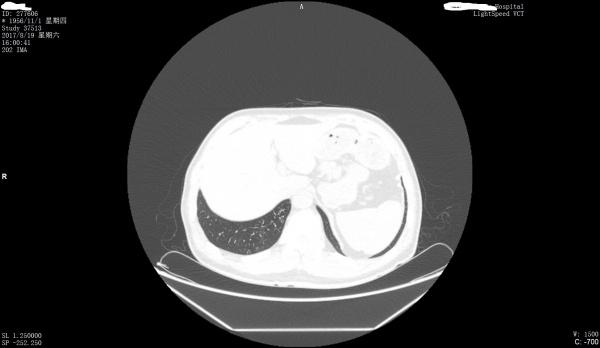

看看是否左膈肌出现胸腹膜裂孔疝

第一上传图片少,第2目前来看只能是疑似。